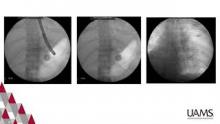

We recommend a fluoroscopy compatible bed as well as C-arm capabilities. A standard EGD scope is needed, as well as an easily accessible pediatric scope. We recommend carbon dioxide insufflation as this is more readily absorbed by the GI tract mucosa and is associated with less postprocedure pain. The instructions for use card provided with the stent should be carefully examined to ensure proper usage. We recommend general anesthesia for this procedure as this facilitates easier placement, protects the airway from possible aspiration, and allows for concurrent bronchoscopy if needed. The patient should be positioned supine with the arms tucked to allow for C-arm movement. The procedure should begin with a diagnostic EGD. Radio-opaque markers are then used to note the GEJ, site of the lesion, and 2cm distal to the lesion. A spring tip guidewire is then placed endoscopically and positioned distal to the lesion.

Choice of stent is guided by the internal diameter and should be slightly larger than the lesion to provide adequate radial force. The stent should overlap the lesion by 2cm proximally and distally. The EGD scope is withdrawn, and the stent deployment apparatus is placed over the guidewire. Proper placement is confirmed with fluoroscopy, and the stent is deployed directly under fluoroscopy. We recommend avoidance of reinstrumentation after deployment, which may dislodge the stent and lead to migration.